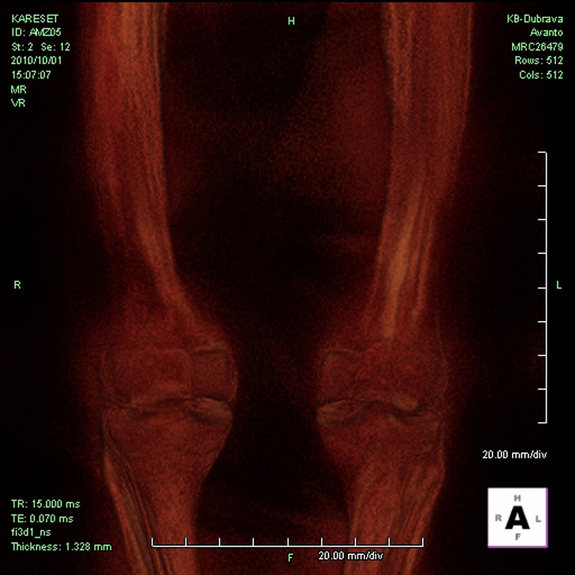

On remarque l'état des genoux de la momie, très abîmés. Il devait en souffrir énormément

On remarque l'état des genoux de la momie, très abîmés. Il devait en souffrir énormément / source : Dr Mislav Cavka